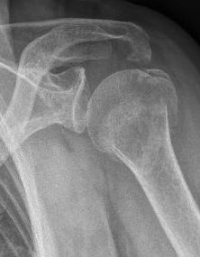

Picture: Here is a subcapital upper arm break in a young woman. An angle stable plate osteosynthesis was performed to stabilize the head in correct position to the humeral shaft and shoulder joint. Especially in young patients, We strive to treat non-invasively and as gently as possible. This possibility is often due to the bone quality in young as opposed to older people.